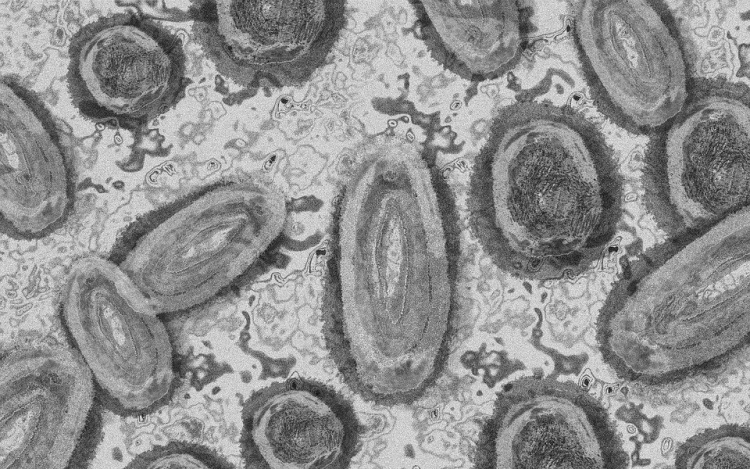

Tovább nőtt a majomhimlő-fertőzöttek száma Magyarországon

Újabb kilenc, 23-50 éves férfinél igazolták a majomhimlő-fertőzést Magyarországon, ezzel 42-re nőtt a fertőzöttek száma - közölte a Nemzeti Népegészségügyi Központ (NNK) csütörtökön az MTI-vel.

A fertőzöttek július 25. és 31. között majomhimlőre utaló tünetekkel keresték fel a területileg illetékes egészségügyi szolgáltatót, ahol minden esetben mintát vettek majomhimlő gyanúja miatt.

A fertőzött emberek otthon tartózkodnak elkülönítve, a legtöbbjük életvitelszerűen Budapesten él - ismertették.

Hozzátették, a területileg illetékes járványügyi hatóság valamennyi beteg esetében járványügyi vizsgálatot, ennek keretében kontaktkutatást végez.

A betegség általános, nem specifikus tünetekkel - lázzal, hidegrázással, izomfájdalommal, hátfájdalommal, fejfájással, fáradtsággal), illetve a nyirokcsomók duzzanatával kezdődik, majd 1-3 nappal a bevezető tünetek után bőrkiütések jelennek meg. A kiütések sok esetben először az arcon, majd a tenyéren és a talpon fordulnak elő, de megjelenhetnek a szájnyálkahártyán, a nemi szerveken és a végbél környékén is - olvasható a közleményben.

A Nemzeti Népegészségügyi Központ arra kéri a lakosságot, hogy kiütéssel járó megbetegedés esetén mindig forduljanak orvoshoz.